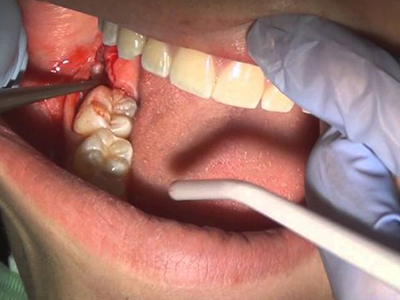

智齿冠周炎智齿周围牙龈肿胀出血图

智齿冠周炎患者第三磨牙萌出不全,日常不易清洁,导致周围牙龈感染,出现牙龈肿胀,肿起的牙龈可包裹磨牙,局部有化脓、出血等炎症表现。